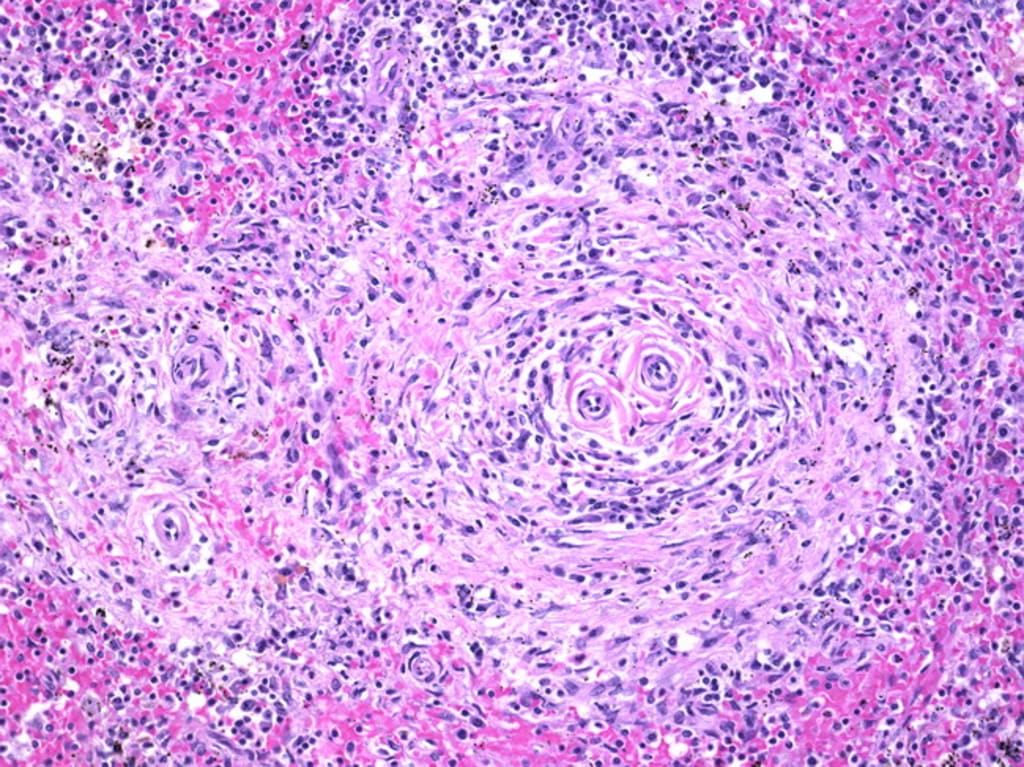

I have an autoimmune disease called Mastocytosis. It’s one of those rare, hard to diagnose and even harder to diagnose, diseases. Basically, it is caused my body having too many mast cells, which have to do with allergies and so on. A case of too much of a good thing being a bad thing. Literally, the only way to treat it would be chemotherapy to get rid of the mast cells, but my hematologist/oncologist thinks that chemotherapy would ruin my life (or at the very least be a bad option) considering that I am only twenty.